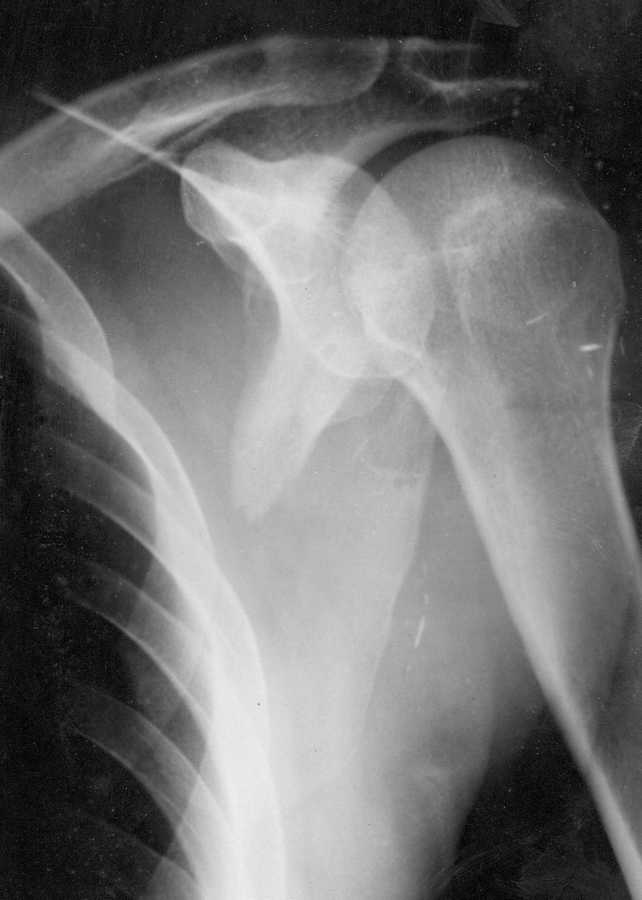

Больной поступил 12.05.09 после избиения битой.При осмотре отёчность в области ости правой лопатки, костная крепитация.

На рентгенограмме перелом латерального края правой лопатки с таким смещением. На других рентгенограммах перелом обеих малоберцовых костей и левой локтевой кости без смещения, множественные ушибы тела. В 2006 году ЧМТ, наблюдается у невролога и психиатра. Находился в РАО. Пока ведётся консервативно на отводящей шины без вытяжения. Какой метод лечения и почему для больного применить?

Здраствуйте, такую лопатку нужно оперировать. Смещение долстаточно приличное для того, чтобы возникли проблемы впоследствии (не только нестабильность, но и импинджементы, в том числе мягкотканые, ограничение отведения, слабость ввиду изменения рычагов ротаторной манжеты). Думаю, что подойдет реконструктивная пластина на латеральному краю лопатки. Доступ можно не только классический, но и задний к плечевому суставу (только его нужно сместить еще чуть кзади), при нем расслаивайте круглую и подостную мышцы вдоль сухожильной перемычки между ними, посмотрите как идет ахиллярный нерв. Удачи.

Если руководствоваться прямой проекцией - лучше прооперировать.

Tckb судить по снимку, то смещение однозначно значительное и при оставлении в таком положении о восстановлении биомеханики плечевого сустава говорить не приходиться. Оперировать без сомнения. С уважением Михаил.